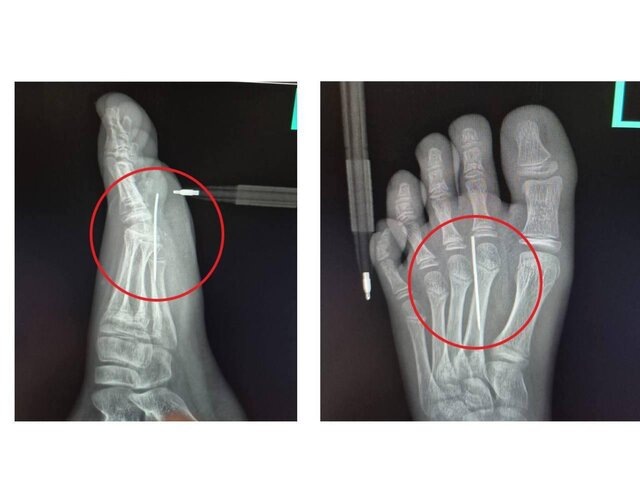

Врачи медучреждения выполнили рентгенографию, по итогам которой подтвердили наличие инородного тела в стопе. Иголка была успешно извлечена при помощи инструмента "Москит". Продолжительность процедуры составила не больше трех минут.